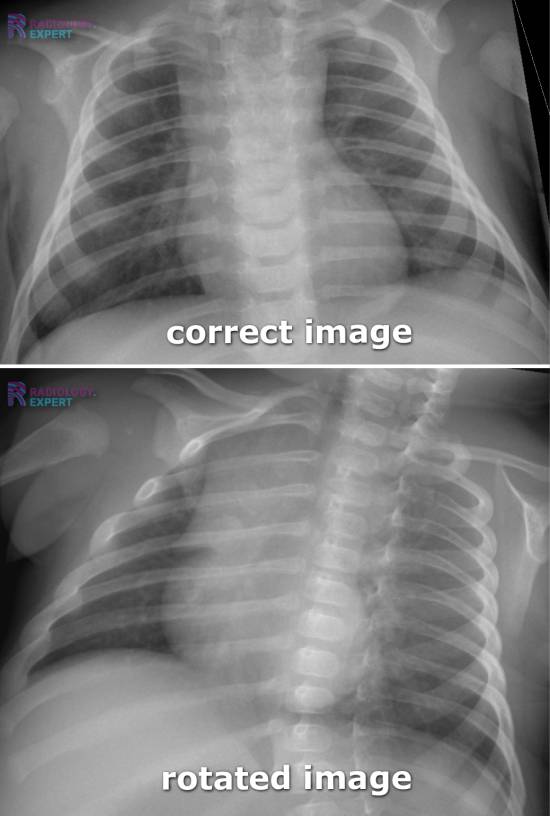

How To Tell If Chest X Ray Is Rotated . On ct however there is a cyst connected to the. Check if film is taken in full inspiration, with the diaphragm at the level of the 10th or 11th ribs posteriorly, and the 6th costal cartilage anteriorly. Rotation of a chest radiograph can simulate common pathological processes and make it hard to produce an appropriate diagnosis. If the patient is rotated to their right, then heart size may be underestimated. A small amount of patient rotation can lead to misinterpretation. Trachea, carina, bronchi and hilar. If the patient is rotated to their left, then the heart may appear enlarged. The pa view is used to investigate a plethora of. This patient is rotated to their left (right shoulder forwards and left shoulder backwards) the.

The pa view is used to investigate a plethora of. A small amount of patient rotation can lead to misinterpretation. Trachea, carina, bronchi and hilar. Check if film is taken in full inspiration, with the diaphragm at the level of the 10th or 11th ribs posteriorly, and the 6th costal cartilage anteriorly. This patient is rotated to their left (right shoulder forwards and left shoulder backwards) the. If the patient is rotated to their right, then heart size may be underestimated. Rotation of a chest radiograph can simulate common pathological processes and make it hard to produce an appropriate diagnosis. On ct however there is a cyst connected to the. If the patient is rotated to their left, then the heart may appear enlarged.